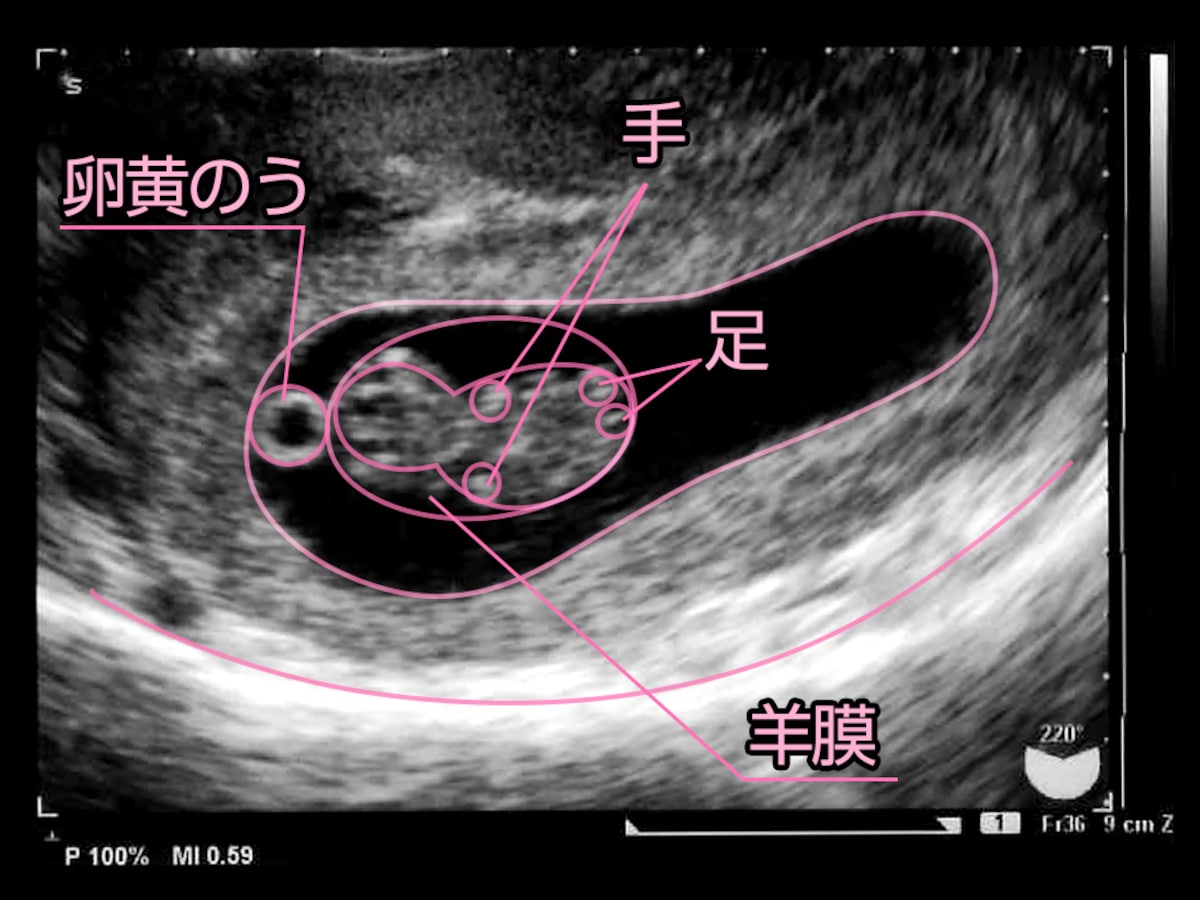

8w0d 胎嚢が狭い 卵黄嚢肥大 流産の兆候 43歳で4人目赤ちゃんを自宅出産しました

超音波写真館 妊娠初期4 7週 超音波教室 ママニティ大百科

8週4日稽留流産 キングサイズの卵黄嚢 腎臓病だけど39歳から始めた第2子不妊治療 40歳 41歳

妊娠6週目 エコー写真 胎芽や胎嚢大きさ 心拍確認や気になる流産 妊娠初期 All About

妊娠8週目 エコー写真や胎児の大きさ平均 つわりや流産症状 妊娠初期 All About

妊娠7週目 胎芽 胎嚢のエコー写真や大きさ つわりや流産 妊娠初期 All About